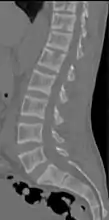

CT scan of the same case.[17]

X-ray of a subtle "rugger jersey spine" due to sclerotic bands adjacent to the vertebral endplates.[17]